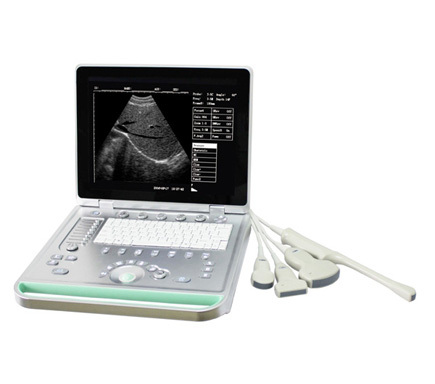

Place of Origin : Shanghai, China

Brand Name : SUCE

Model Number : SU-7S

Packaging Details : carton box/wooden box

Supply Ability : 1000 Piece/Pieces per Month

Price : $1,250.00 - $1,350.00/Pieces

Certification : CE,ISO13485

MOQ : 1PC

Payment Terms : T/T, Western Union,Payoneer

Delivery Time : about 5 days

Instrument classification : Class II

Type : Doppler Ultrasound Equipment

Display : 15 inch LCD screen

Working frequency : 2.0MHz~10MHz

Scanning range : Convex array 60°~150°

Amplification factor : 1.0, 1.2, 1.5,2.0

Image gray-scale : 256 levels

Scanning line number : 512 lines/frame

Frame rate : 30 frames/second

Port : Shanghai

Feature:

-15 inch LCD screen

-Full digital imaging technology, crystal-clear Image

-Pretty and light

-8 segment TGC

-Broadband multi-frequency probes

-2 probe connector

-Silica gel backlight gravure laser keyboard

-USB flash disk large volume image storage

-Cine loop

-Built-in battery(can work more than 5 hours)

-High Cost-effective

Standard configuration:

One host, one convex probe, one aluminum trunk

Optional:

Transvaginal, linear, micro-convex probe;

Biopsy; Trolley; Printer.

Portable ultrasound machine Laptop Ultrasound machine SU-7S with CE Images |